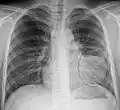

- Normal AP CXR

Normal lateral CXR

AP CXR showing left lower lobe pneumonia associated with a small left sided pleural effusion

AP CXR showing right lower lobe pneumonia

AP CXR showing pneumonia of the lingula of the left lung

Right upper lobe pneumonia as marked by the circle.- Left upper lobe pneumonia with a small pleural effusion.

- Right lower lobe pneumonia as seen on a lateral CXR